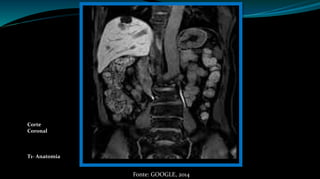

Corte

Coronal

T1- Anatomia

Fonte: GOOGLE, 2014

Corte Coronal T1-Anatomia Fonte: GOOGLE, 2014